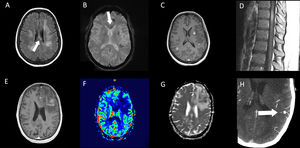

On cranial magnetic resonance imaging (MRI) (Fig. 1), the findings were (Table 1): multiple lesions in white matter and corpus callosum (some of them with enhancement and others with hemorrhagic foci) and multifocal infarcts with hemorrhagic transformation. Leptomeningeal branch aneurysms were found in patient 3. In two patients with spinal cord syndrome, the spinal cord MRI showed lesions with enhancement. A PET-FDG was performed in five patients showing various areas of elevated uptake in all of them (Fig. 2). Three patients underwent random skin biopsies, which were normal. In patient 1, the diagnosis was made by muscle biopsy. Targeted biopsy after PET-FDG findings was performed in four patients, which allowed the diagnosis of IVL to be established in three. One patient with pathological PET-FDG could not undergo solid organ biopsy because of severe thrombopenia and the diagnosis was established by coxal biopsy. One patient was diagnosed postmortem. In this last patient, a diagnosis was not reached despite pancreatic biopsy due to the fibrohematic content not suitable for analysis, although the suspicion of IVL had already been established during his lifetime.

Proton emission tomography with fluorodeoxyglucose (PET-FDG) of two different patients. Patient 3 (A) PET-FDG (top row) and PET/computed tomography (CT) fusion (bottom row) showing focal increased uptake within adrenal glands. Patient 4 (B) PET-FDG (top row) and PET/CT fusion (bottom row) showing focal increased uptake within both kidneys, predominantly in the left.